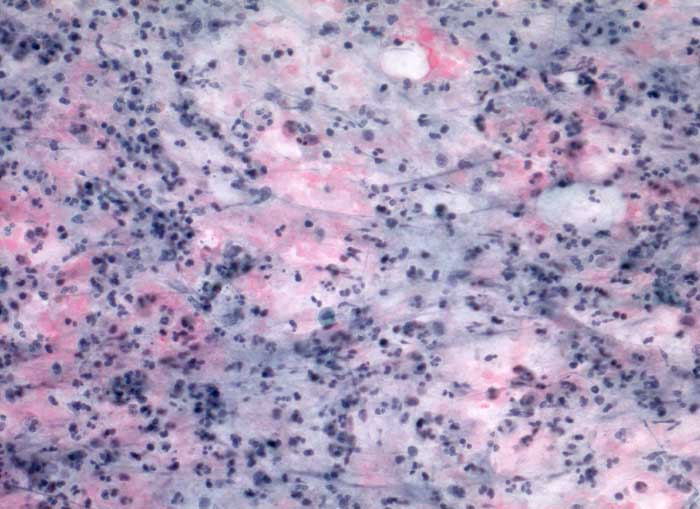

PathoPic ID 5442 - akute Sialadenitis

akute Sialadenitis

Entzündung / Reparatur

Parotis

Kopf & Hals, Sinnesorgane

Feinnadelpunktion Parotis: Im Hintergrund amorphes eiweissartiges Material. Massenhaft neutrophile Granulozyten und Makrophagen.

Akute Entzündung der Speicheldrüse DD: maligner Tumor

Keine histologische Untersuchung notwendig

Zytologie

200